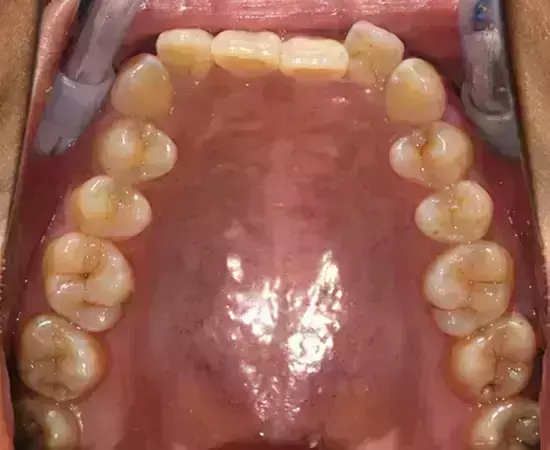

Damon 病例分享:安氏 II 類(lèi)二分類(lèi)露齦笑的矯治(董一磊)

患者信息

治療前后對(duì)比